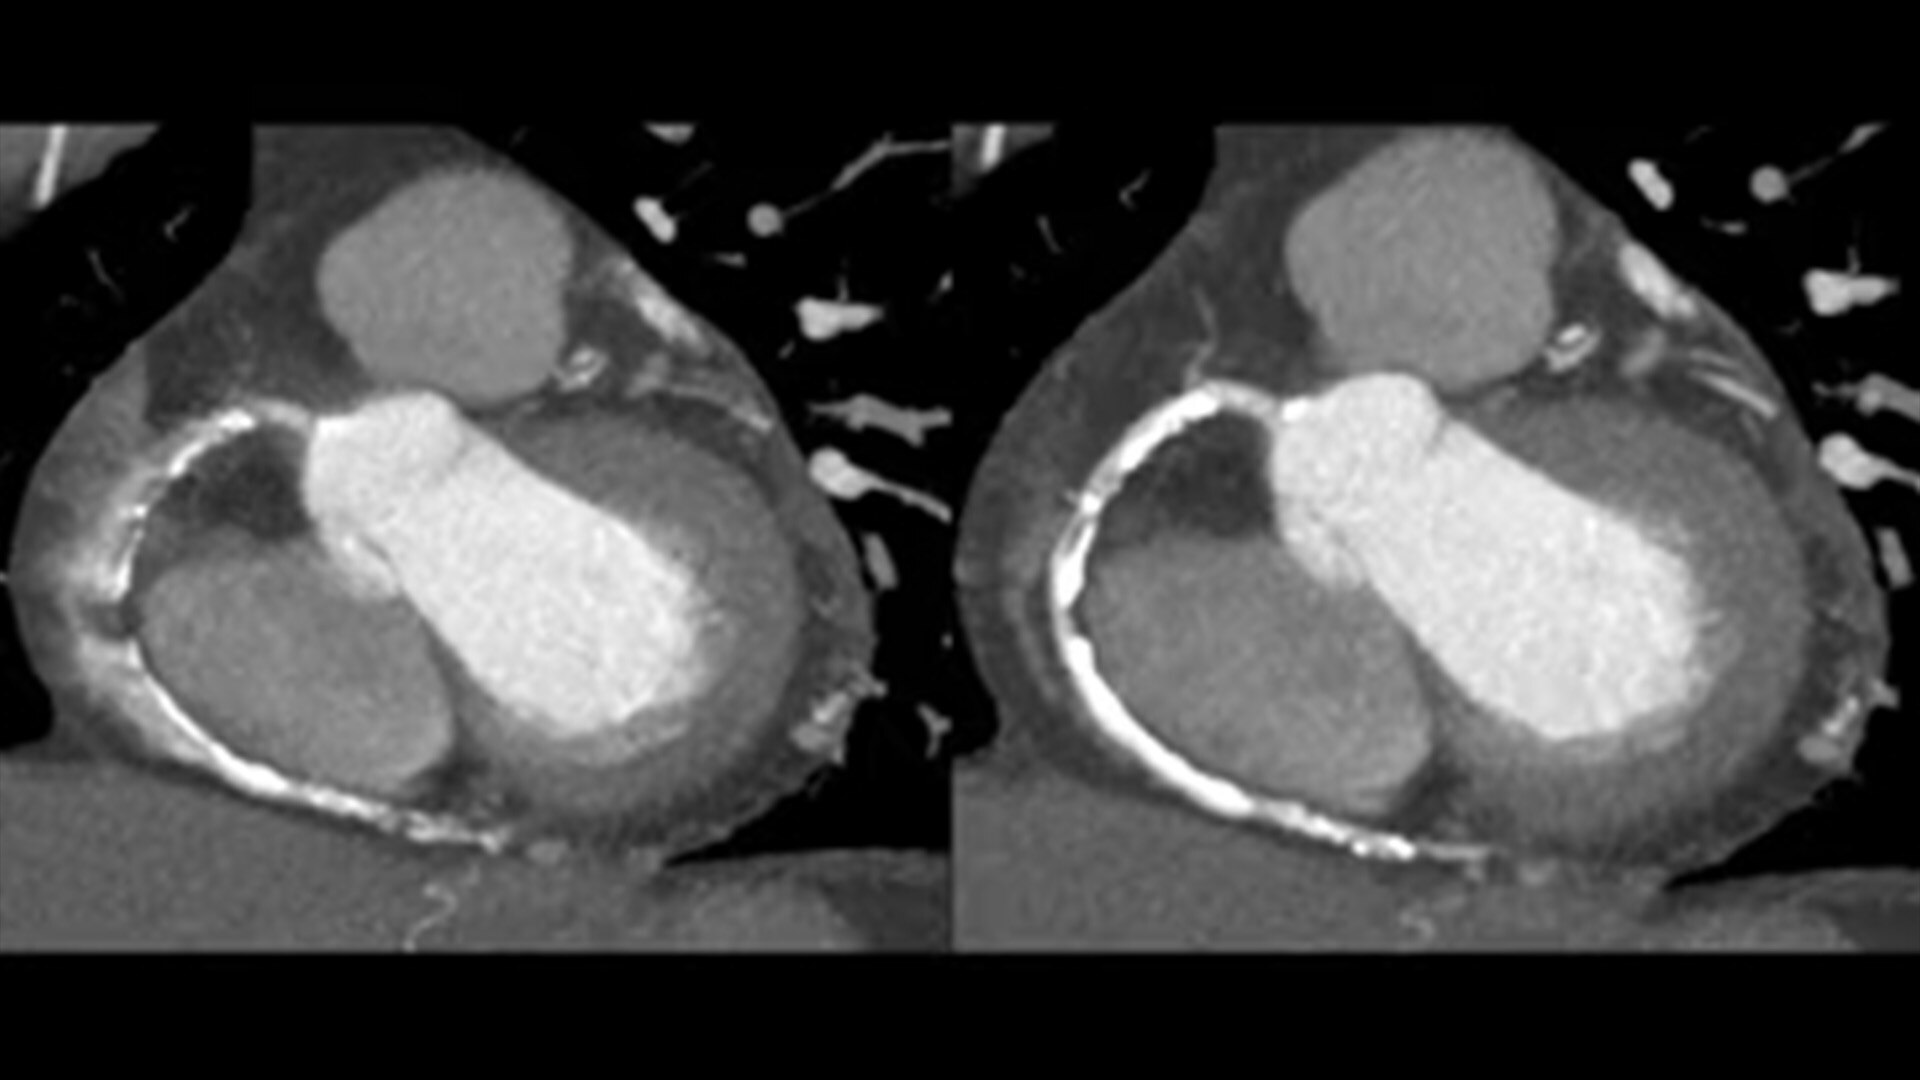

SnapShot Freeze 2

Intelligent and automated whole-heart motion correction for enhanced Cardiac CT imaging.

Motion correction

6x reduction in motion artifacts1

Temporal resolution

19.5 msec effective temporal resolution at 0.23s/rotation gantry speed2